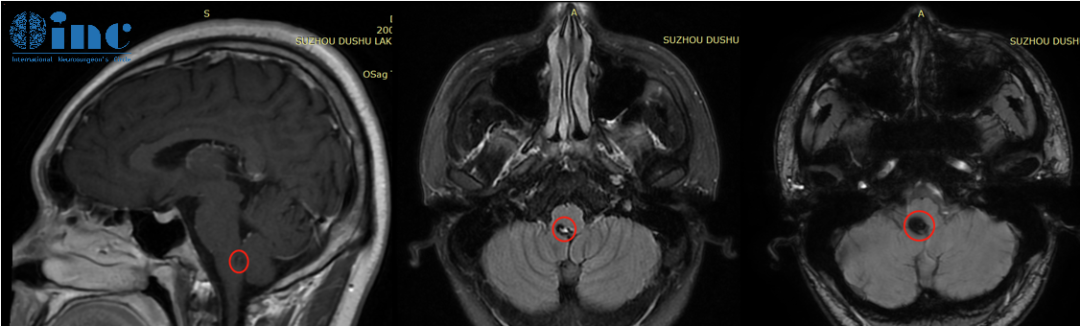

但是卻不想竟是“生命中樞”——腦干上出了問(wèn)題。頭部CT顯示延髓后方近小腦見(jiàn)大小約6.8*9.9mm的片狀高密度陰影,懷疑腦干海綿狀血管瘤。

腦干海綿狀血管瘤患者案例——影像